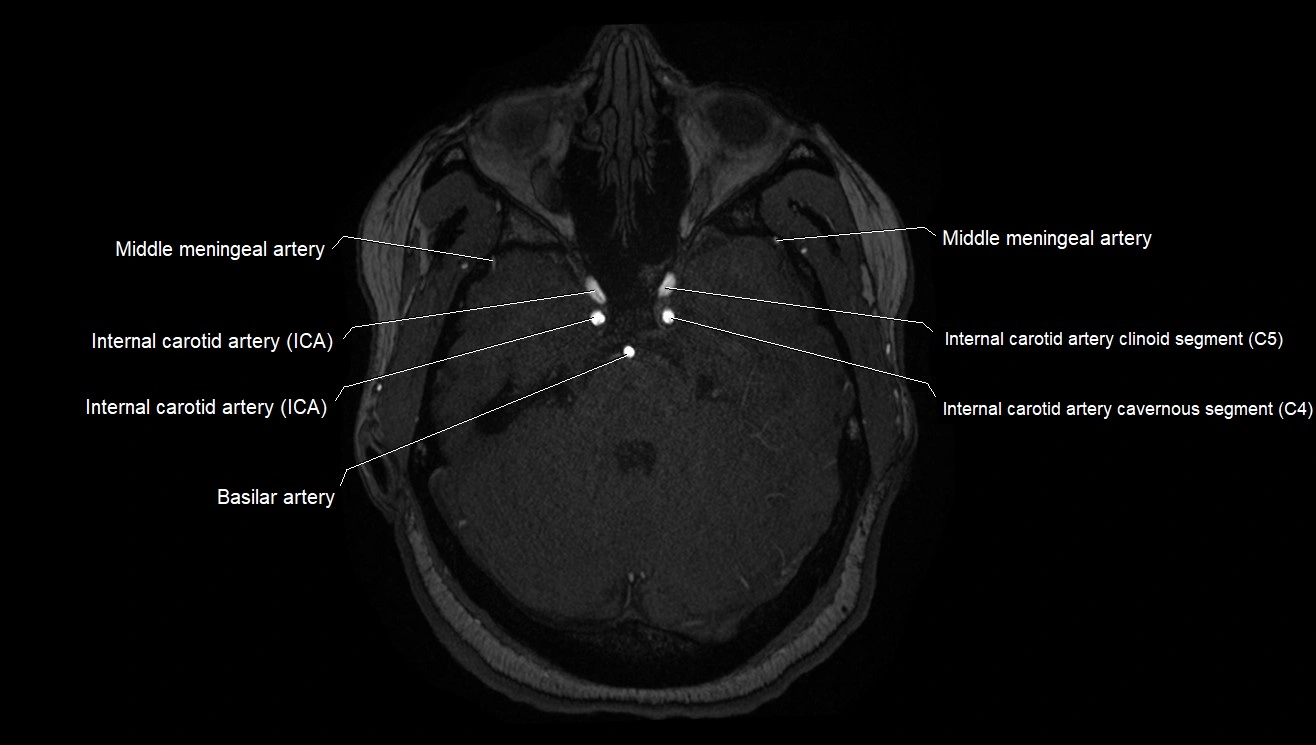

MRA (Magnetic Resonance Angiography):

• Flow-related enhancement makes the AChA appear as a bright, linear vascular signal against suppressed background

• High sensitivity for origin and proximal course; distal branches may be too small to resolve

• Detects stenosis, occlusion, aneurysm, AVM feeders

MRI images

image